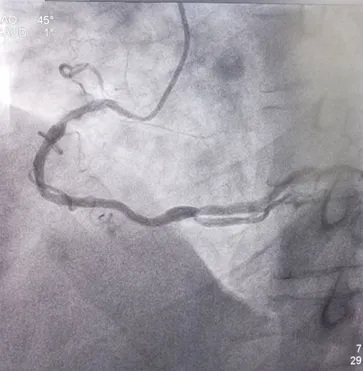

冠脉造影:入院第8天

左前斜位:RCA近段50%狭窄;PDA开口局限性狭窄约60%

造影结果:冠脉多支病变,LAD近、中段50%狭窄,LCX 中段75%狭窄,D2 近段70%狭窄RCA近段50%狭窄,PDA近段60%狭窄。

患者多支血管病变,行FFR检查LCX :0.78,D2:0.77治疗策略:暂可以不行PCI治疗,继续纠正心衰治疗。